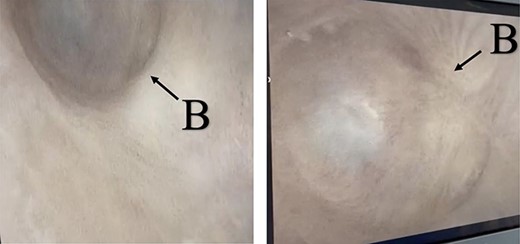

A 38-year-old male was referred to our tertiary hospital due to recurrent urethral stricture for further evaluation and management. His history revealed multiple failed attempts of DVIU, anastomotic urethroplasty and urethroplasty with pedicled fasciocutaneous flap in 2019. Nine months after his surgery, he had complete retention due to stricture recurrence and he underwent multiple dilatations and DVIU but his stricture keep recurring. He was referred to us for definitive management. He was on a suprapubic catheter. Initial workup included retrograde, antegrade cystoscopy and urethrogram. First, an antegrade cystoscope was introduced. The bladder neck, internal sphincter and verumontanum were identified. However, there was no external sphincter due to damage from the previous procedures. A pinpoint opening in the dorsal area of the urethra was seen about 1-cm distal to the verumontanum (Fig. 1, lumen A). Also, a blind-ended urethra in the ventral area was identified (Fig. 2, lumen B). It is most likely from the previous flap. Additionally, the retrograde urethrogram showed that the contrast was only going from the pinpoint hole in the dorsal side of the urethra Fig. 3. Retrograde cystoscopy also showed a blind-ended in the proximal bulbar urethra. We could not identify the small hole that we saw from the antegrade cystoscopy. After initial workup, he was counseled in the clinic for dorsal only buccal mucosal graft (BMG) urethroplasty for which he agreed.

(lumen A): A pinpoint opening in the dorsal area of the urethra as pointed in the arrow.

(lumen B): A blind-ended urethra in the ventral area of the urethra as pointed in the arrow.